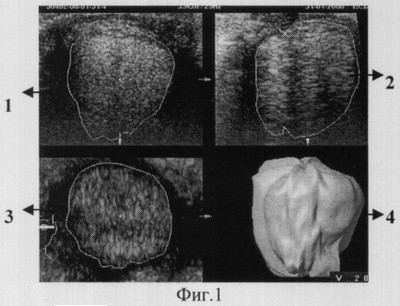

Краткое описание чертежей: На фиг.1 представлено сканирование имплантата в горизонтальной плоскости; на фиг.2 – сканирование в вертикальной плоскости; на фиг.3 представлено сканирование в диагональной плоскости от верхневнутреннего к нижненаружному углу; на фиг.4 – сканирование имплантата в диагональной плоскости от верхненаружного к нижневнутреннему углу. На всех вышеуказанных фигурах: 1, 2, 3 – выделенные УЗ-срезы с наиболее четким изображением, 4 – смоделированные имплантаты для каждой плоскости сканирования. На фиг.5 представлена трехмерная модель имплантата; на фиг.6 – структура имплантата; на фиг.7 – положение имплантата в склеральном мешке в горизонтальном срезе; фиг.8 – вид структуры имплантата в разных плоскостях; на фиг.9 – эхограмма орбиты в горизонтальной плоскости через 6 месяцев после операции, цветовая карта сосудов в толще имплантата; на фиг.10 показана трехмерная модель имплантата через 6 месяцев после операции; на фиг.11 – децитометрические характеристики разных участков имплантата в ранние сроки после операции; на фиг.12 – трехмерная модель имплантата через 2 месяца после энуклеации.

Способ осуществляется следующим образом: Исследование выполняют на ультразвуковых цифровых диагностических системах общеклинического назначения с режимом объемного сканирования, например на приборе Voluson 730. Над исследуемой орбитой пациента помещают сканирующий датчик таким образом, чтобы плоскость сканирования располагалась в определенном направлении. Способ иллюстрируется на фиг.1-4, где а, b, с – выделенные ультразвуковые срезы имплантата с наиболее четким изображением; d – трехмерная модель имплантата, характерная для этой плоскости, которую получают путем виртуальной ротации с шагом 6-30°. Вначале производят сканирование в горизонтальном направлении (фиг.1), затем перемещают датчик, чтобы плоскость сканирования располагалась в вертикальном направлении (фиг.2). Следующие исследования выполняют помещая сканирующий датчик в диагональных плоскостях – от верхневнутреннего к нижненаружному углу орбиты (фиг.3) и от верхненаружного к нижневнутренему углу орбиты (фиг.4). Томографию производят сначала при взгляде прямо и при максимальных отведениях взора в тех же плоскостях. Всего производят 36 сканирований (в 4 плоскостях по 9 различным направлениям взора: прямо – 1, в вертикальном – 2, горизонтальном – 2, диагональном – 4). Такое количество сканирующих срезов необходимо, так как после удаления глазного яблока и формирования опорно-двигательной культи исследования проводятся в условиях нарушенной архитектоники орбиты, при этом выводится на осмотр крайняя периферия культи, труднодоступная для исследования при взгляде прямо и сканировании только в одной плоскости. Поскольку для каждого пациента моделируется индивидуальный имплантат во время операции, то его форма всегда бывает несколько отличающейся от идеально сферичной или идеально конической формы, соответственно изменениям мягких тканей орбиты. При этом для каждой пространственной позиции выделяют характерный для нее срез имплантата, по которому впоследствии путем виртуальной ротации с шагом 6-30° моделируют объем имплантата (фиг.5) и из всех полученных показателей объемов вычисляют средний. При суммарном анализе сканирующих срезов в различных плоскостях (фиг.6) и при различных отведениях оценивают взаимоотношение имплантата с окружающими его тканями по плотности зоны их контакта, по величине расстояния между ними и по ширине окружающих имплантат тканей. Далее оценивают структуру имплантата по показателям однородности, плотности и наличия сосудов. Динамику прорастания имплантата соединительной тканью анализируют по изменению эхографической плотности материала имплантата, а также по расстоянию между имплантатом и его капсулой (склерой). По показателю однородности распределения плотности материала имплантата судят о динамике интеграции отдельных фрагментов имплантата в единый конгломерат.